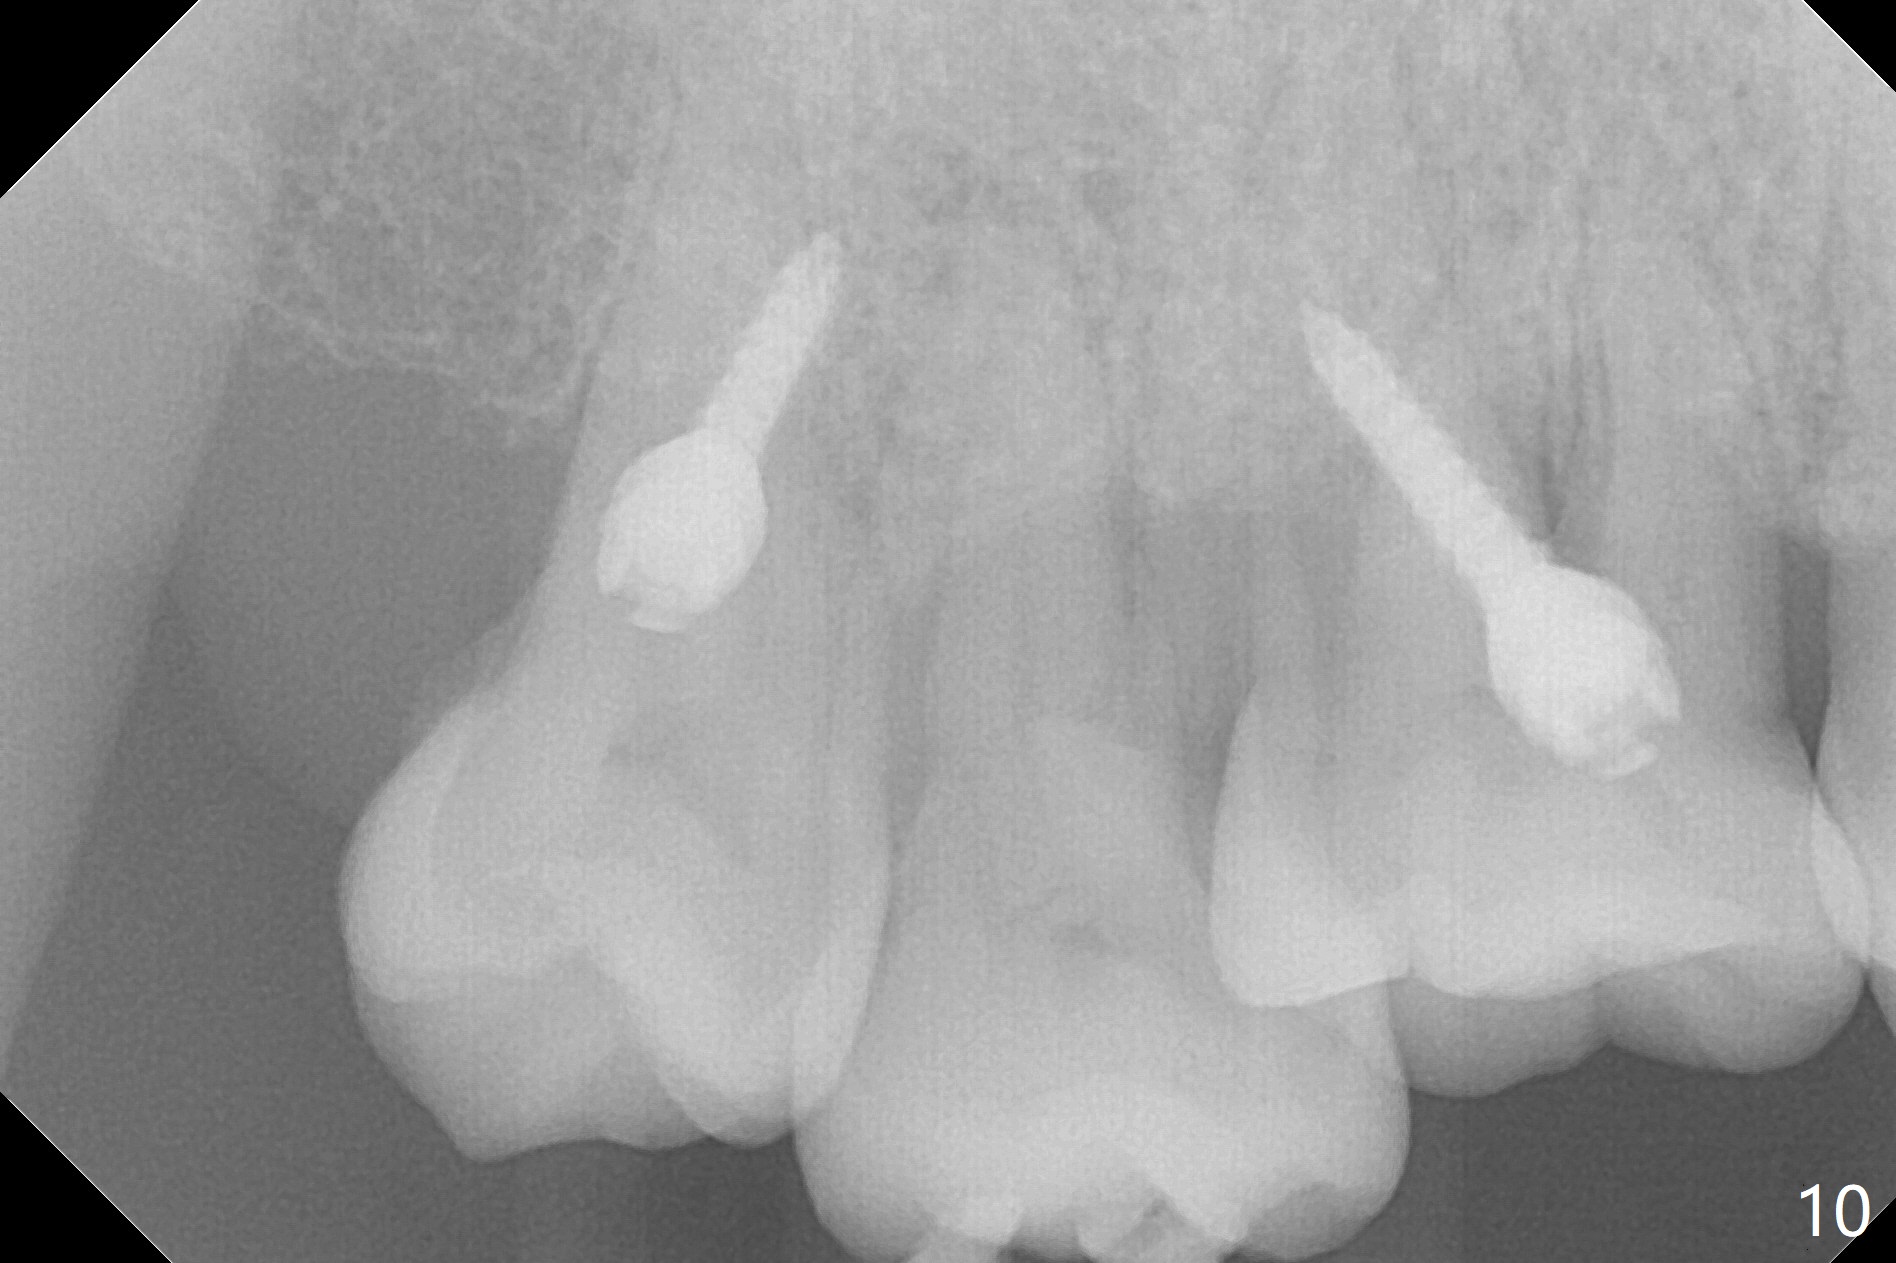

Two days post #31 implant placement, the patient returns for orthodontic intrusion of the tooth #2 with mini-implants (Fig.1). The palatal cusps have been trimmed (Fig.2 ^), since they almost contact a healing abutment at #31(*, Fig.3). Two mini-implants are to be placed mesiobuccal and distopalatal to the affected tooth. After minimal injection of Lidocaine, a 1.6x6 mm Tomas implant is placed in full length mesially (Fig.4), while the other (1.6x8 mm) half way (Fig.4). Following change in implant site mesially (Fig.6 >), the implant is half inserted (Fig.5). It appears that the tip of the distal implant is toward the tooth #1 (Fig.5). After withdrawing the implant partially, it is re-directed to apparently ideal trajectory (Fig.7). Ideally the mesial implant (Fig.8) should have been placed partially initially (Fig.4,5,7) so that the trajectory could have been able to be changed.

The buccal implant becomes loose in 2-3 months. When the wound heals (Fig.9 <), a 1.6x`10 mm implant is placed with the help of PAs for trajectory (Fig.10,11) and in the nonkeratinized gingiva (higher, the crestal bone may have been traumatized by previous implant placement, Fig.12). Two months later, the tooth #2 is partially intruded (Fig.13). A provisional (Fig.14 P) is fabricated in the osteointegrated implant at #31 with supraocclusion so that the remaining dentition has no occlusal contact (*). The periodontally compromised tooth #2 becomes in buccoversion in 2 months. The provisional is removed, while a lingual button is placed in the buccal surface of the tooth #2 (Fig.15). With power chain attached to the lingual mini-implant, the tooth #2 is lingualized in 2 months. The provisional and the implants are reused for final intrusion (Fig.16). The treatment is nearly 11 months. The buccal implant, although placed in the movable mucosa, remains stable and healthy (Fig.17). The tooth #1, as a guiding plane (to prevent #2 from distalization during intrusion), is not extracted after intrusion is completed.